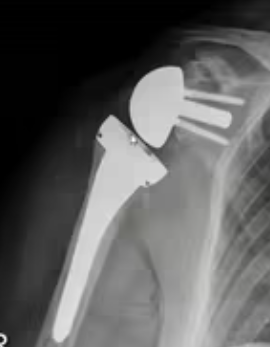

L’idea di invertire la struttura anatomica della protesi, portando cioè la parte sferica sulla glena e la parte concava sull’omero,( protesi di spalla “inversa”) ha portato ad avere un impianto che funziona perfettamente anche senza cuffia dei rotatori grazie alla sua stabilità intrinseca.

La protesi inversa

La protesi di spalla inversa sta diventando di uso molto frequente arrivando ad essere il 95% delle protesi impiantate nella spalla.